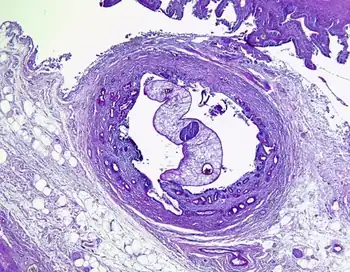

| Opisthorchis sp. in Luschka's duct | |